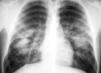

Medicina Clínica «Pulmón de crack»

«Pulmón de crack»

«Crack lung»